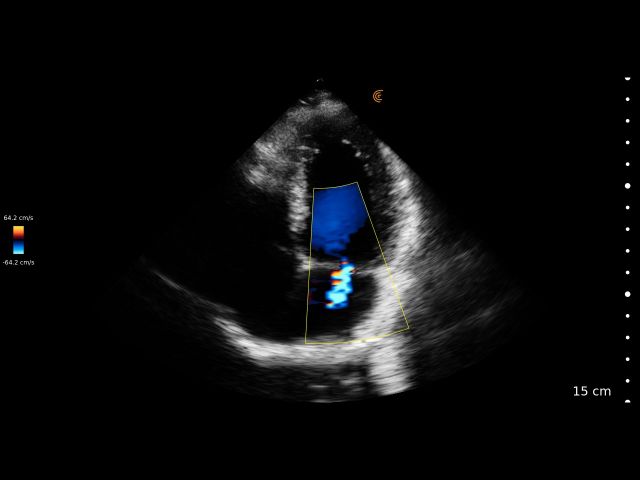

Medical professionals love the high portability, easy of use, and high-definition imaging of the Clarius C3 HD3 multipurpose scanner for full body imaging up to 40 cm. It’s the leading choice for medical professionals looking for premium imaging in an affordable scanner. Artificial intelligence, specialized presets and customizable workflows automatically optimize imaging for a seamless experience.

Applications: Abdominal, Cardiac, Lung, OB/GYN, Superficial

Clinical Images